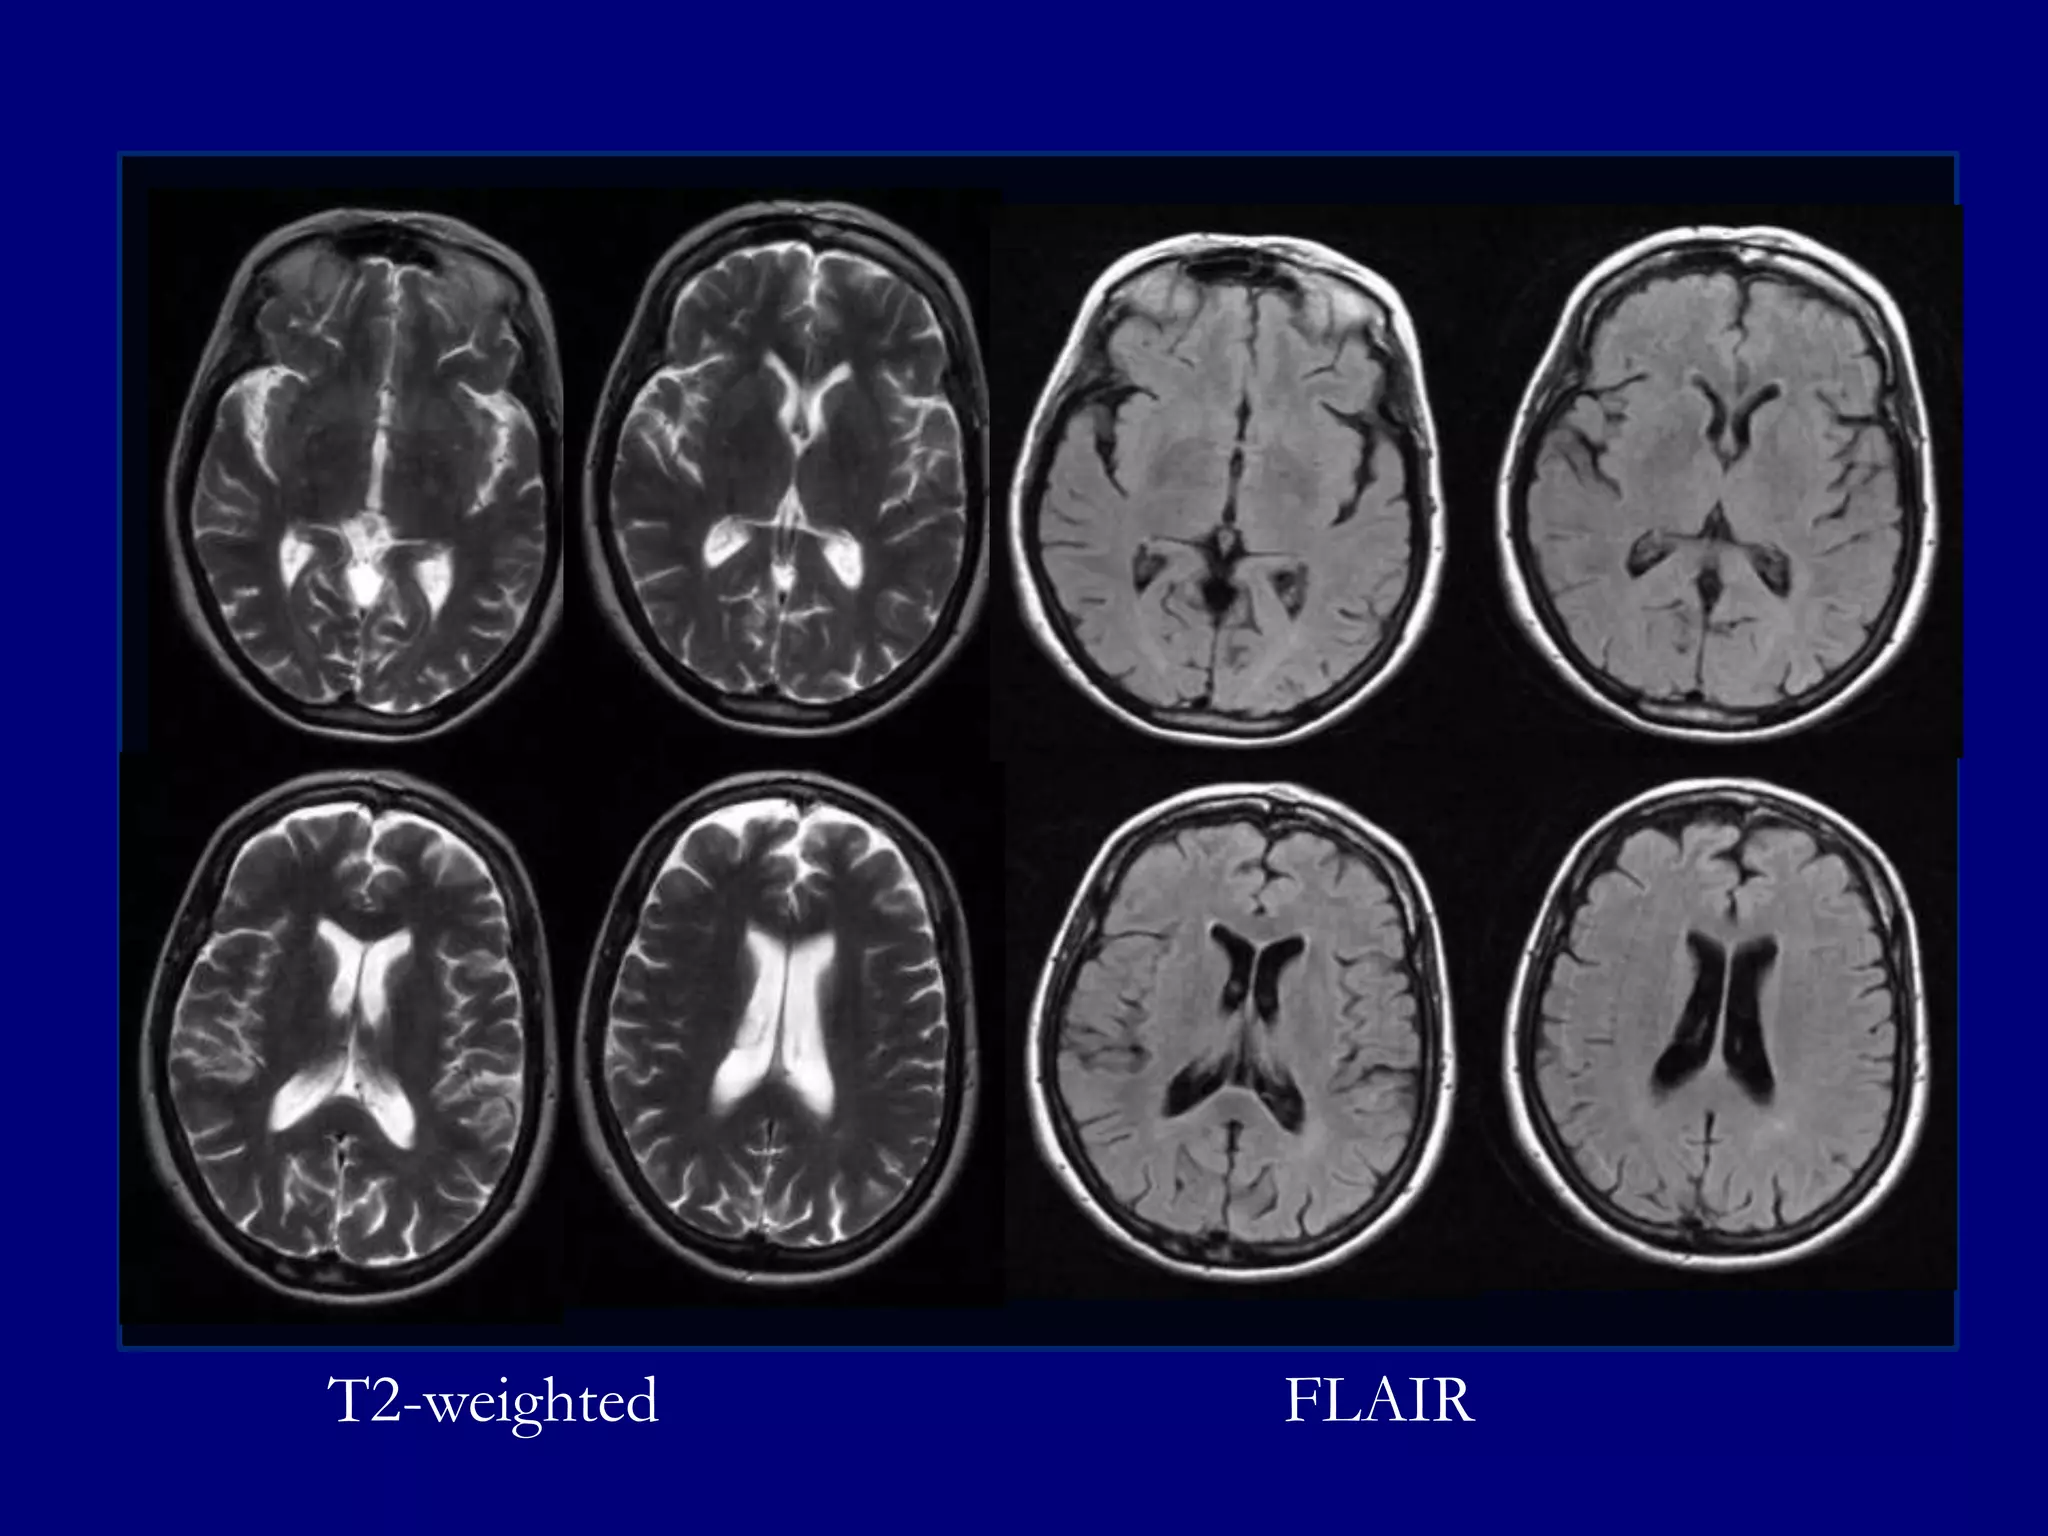

Magnetic Resonance Imaging

T2-weighted Images

FLAIR

MRI

Low signal central portion on T1 and T2-weighted

images indicating fibrosis

 Enhancement at the margins suggestive of

hemangiomatous active component of the disease